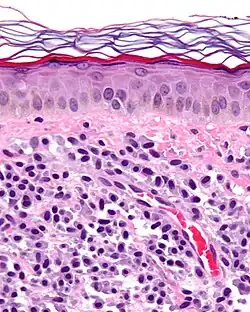

| Micrograph of mastocytosis. Skin biopsy. H&E stain. | |